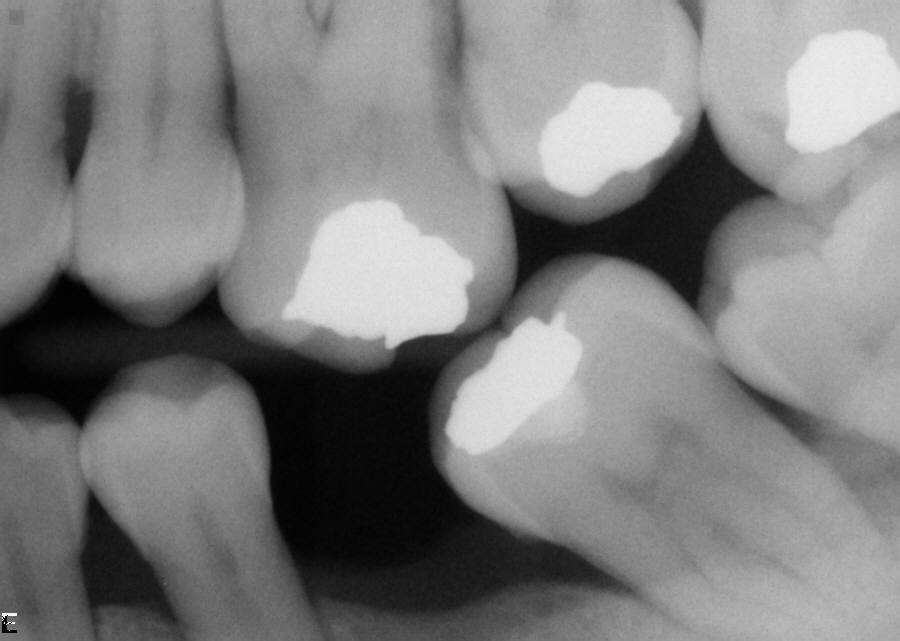

This molar is extensively decayed at the back, extending into the nerve space. Options are to root treat it (endodontics) or extract it.

Three canals were successfully filled with the infection eliminated. The tooth was rebuilt and now has a good prognosis.